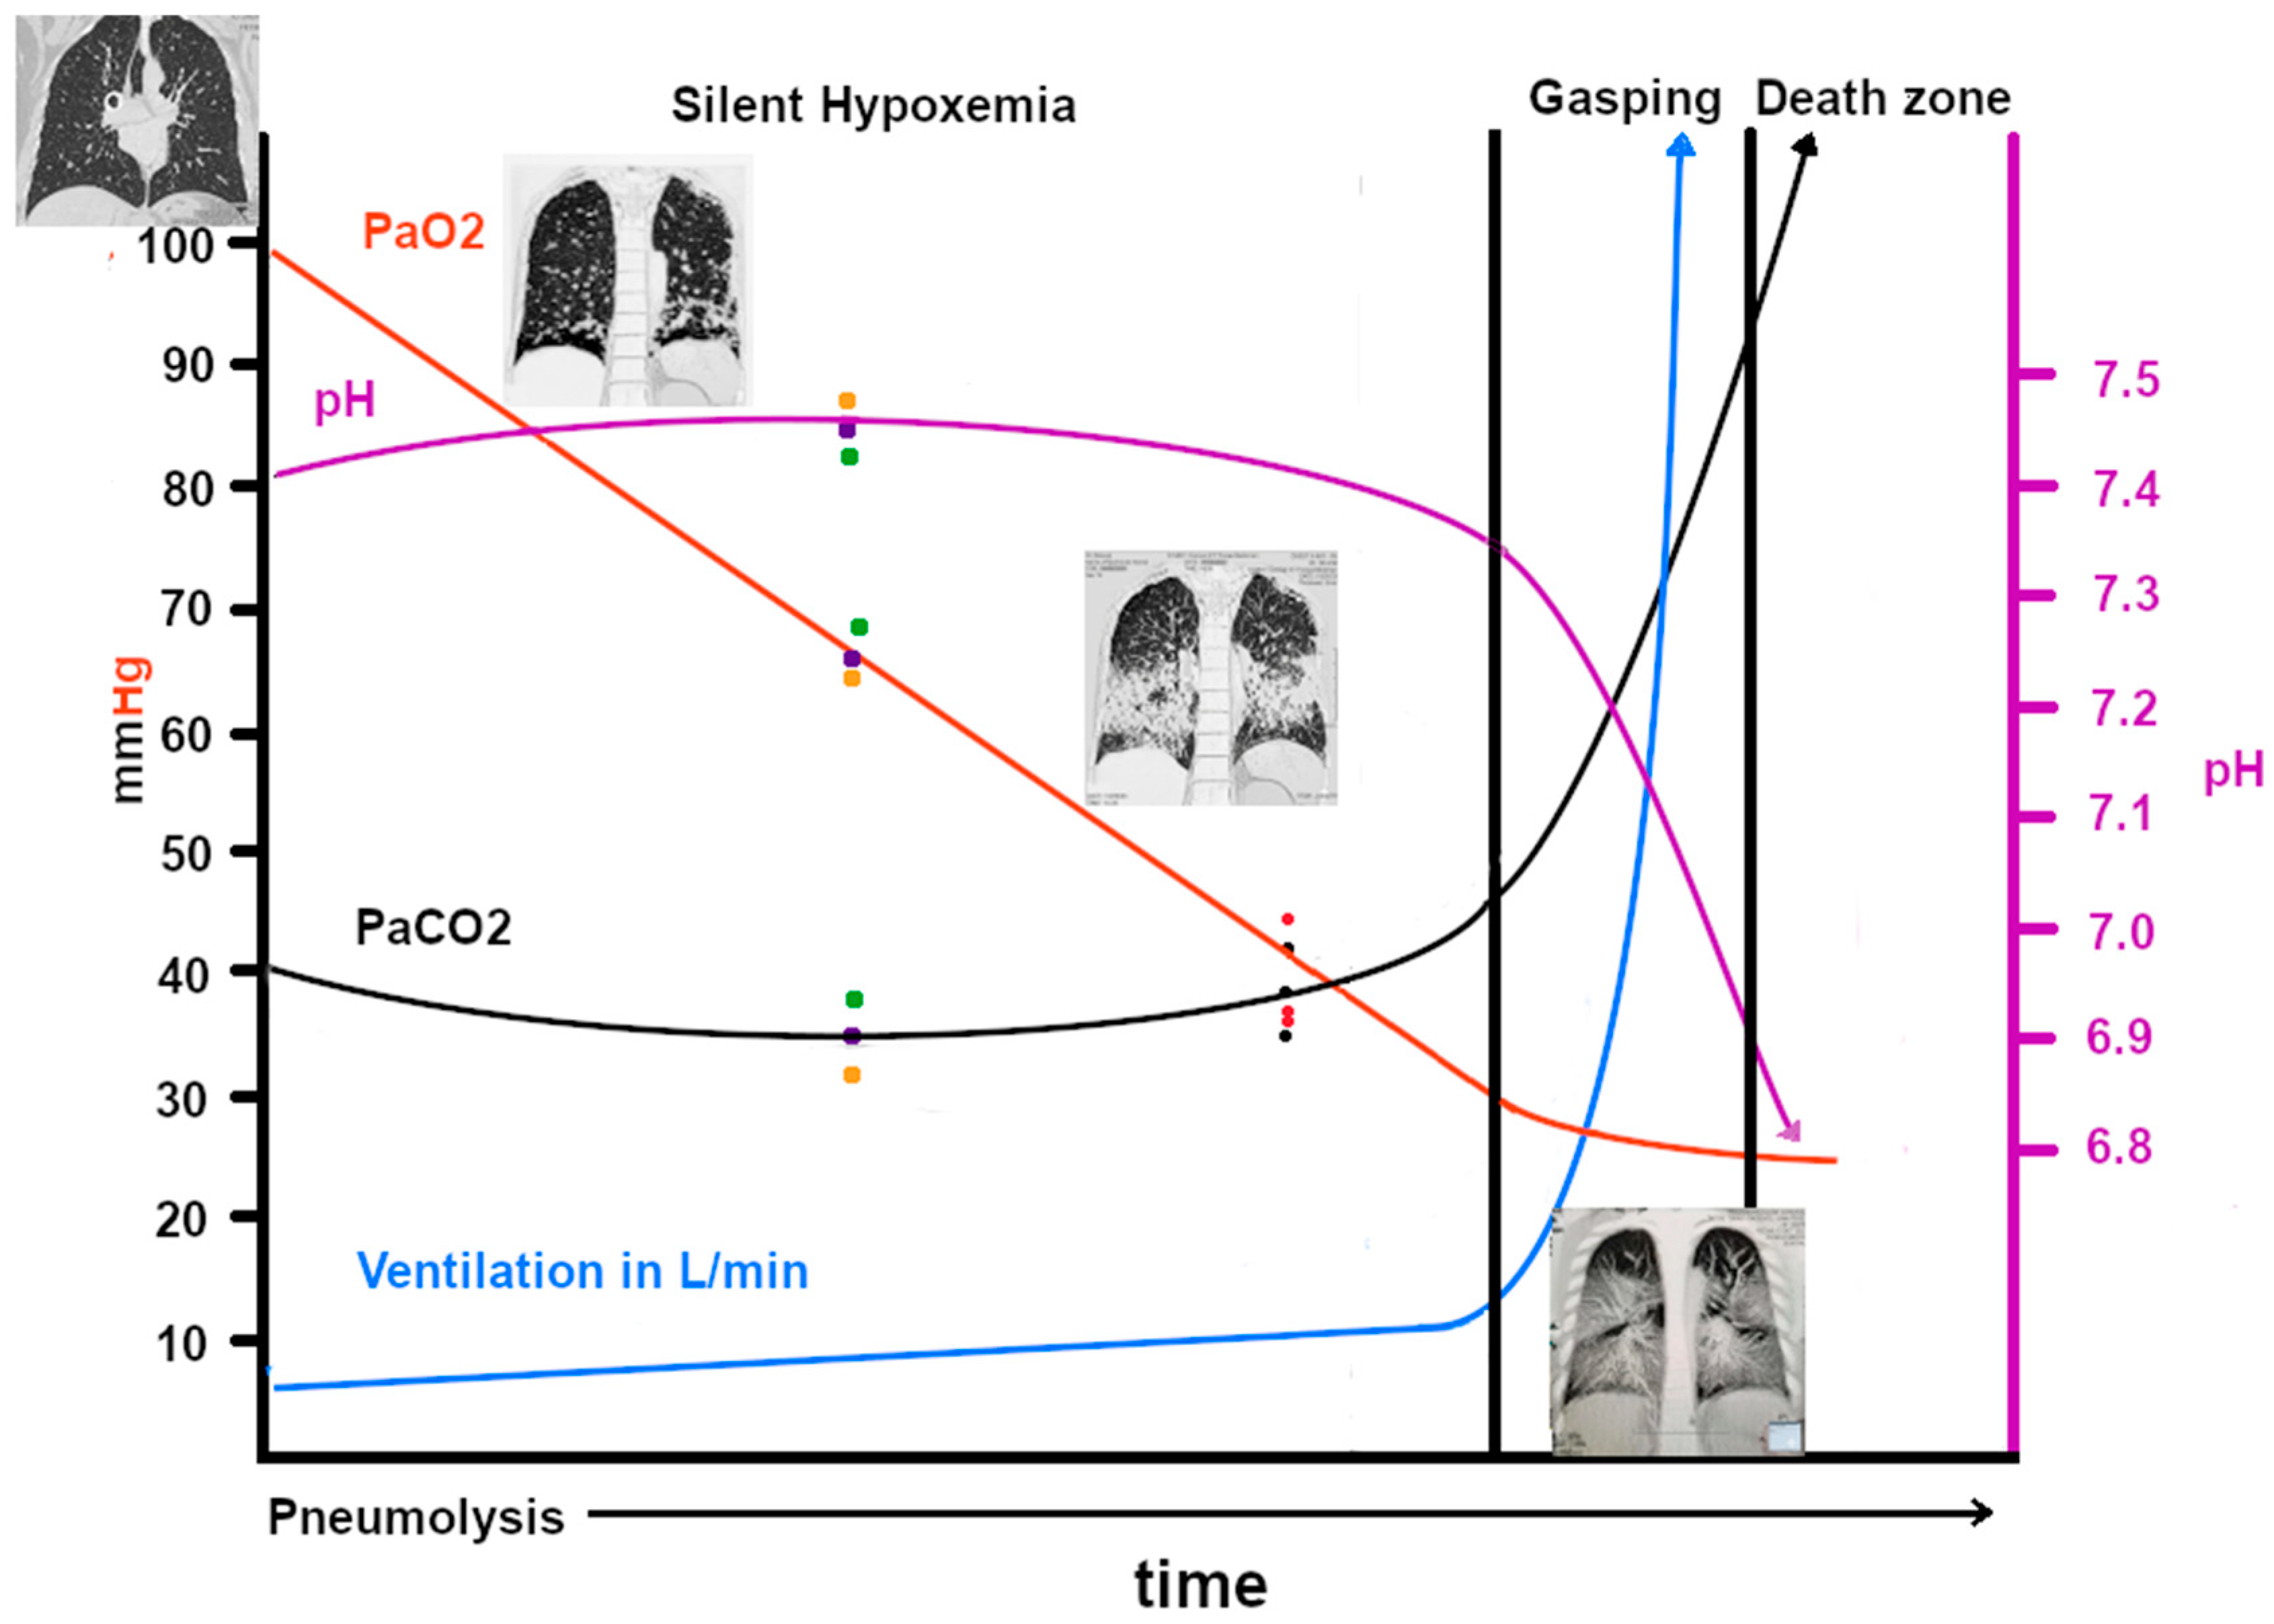

Figure 7.

This graph, developed by both Zubieta authors, shows the probable blood gases, acid–base, ventilation, and hypoxemia evolution in COVID-19 disease at sea level. Note that the pH scale is on the right and the PaO2, PaCO2 and ventilation scales are on the left. The CT scan images (courtesy of Centro de Estudios Tomográficos CET La Paz, Bolivia) show how, as the disease spreads throughout the lungs, the gas-exchange compromise increases, thereby reducing the oxygen transport through the alveolar–capillary membrane. The green, black, and yellow dots represent actual blood gases obtained from https://www.youtube.com/watch?v=_KMLW8eO0q0 (accessed on 28 December 2025) by Dr. Shiv Kumar Singh. The black and red dots are from [39].

COVID-19 patients often show a predominance of pneumolysis in the lower lobes of both lungs. The probable explanation may relate to aerodynamics and lung elasticity, which initially respond by distending the lower lobes on inhalation due to diaphragmatic contraction and the direct orientation of the main bronchi, thereby directing SARS-CoV-2 to the base of the lungs. COVID-19 lung injury involves direct viral epithelial cell damage and thrombotic and inflammatory reactions. There are differences between ARDS and COVID-19 lung injury in aspects of aeration distribution, perfusion, and pulmonary vascular responses [84]. It has been established that angiotensin-converting enzyme 2 (ACE-2) is the cellular receptor for severe acute respiratory syndrome–coronavirus (SARS-CoV) and the new coronavirus (SARS-CoV-2) [85]. SARS-CoV-2 enters type 2 pneumocytes [86], and since these cells are next to type 1 pneumocytes and sustain them, they are destroyed, and the whole alveolar structure is seriously compromised, as evidenced in several studies. The possible pathophysiological responses have been described in a paper entitled “Pneumolysis and Silent Hypoxemia” [18]. Figure 7 shows the pathophysiologic changes in COVID-19. Some newspaper interviews and publications in a local bulletin in La Paz, Bolivia, have informed the public about this new terminology and its implications [28].

However, as the disease progresses, all three hypoxia-producing conditions are present (diffusion, ventilation/perfusion inequality, and, above all, shunts), and it is for this reason that supplementary oxygen is unable to raise the SpO2 to normal levels (98% at sea level and 90% at 3500 m of altitude). Carbon dioxide (20 times more diffusible than oxygen) can still be adequately ventilated and expelled despite the significant reduction in the oxygen exchange surface (Figure 6). However, when the lung exchange surface is seriously compromised, the lung is unable to eliminate excess carbon dioxide [87], and this is when gasping occurs (Figure 6). It is essential to observe that the SpO2 falls linearly as the expansion of the pneumocyte invasion of SARS-CoV-2 evolves. We initially thought it would be a curve; however, based on actual blood gas data, it was concluded that it was most probably linear.

Originally, we also observed that there were not many changes in pH or PaCO2 in the “silent hypoxemia” phase [18], with mild hyperventilation as also described by [39]. The latter points out fundamental aspects; however, the whole picture is incomplete. In our experience, high-altitude residents at 3600 m (as at any altitude) actually live with a permanent “silent hypoxemia”. With this experience, we are able to propose the explanation of the baffling “silent hypoxemia” in COVID-19. It is for this reason that we postulate that during acute hypoxemia with the impossibility of raising PaO2 and SpO2, a fundamental solution in order to save lives would be to use of extracorporeal oxygenation [18] and the administration of erythropoietin.

The pathophysiology of COVID-19 at high altitude is shown in Figure 8, where the starting PaO2 is 60 mmHg at 3500 m. The descent to critical hypoxia is not as steep as at sea level. This could help explain the lower incidence of COVID-19-related deaths at high altitudes.

This graph shows the probable blood gases, acid–base, ventilation, and hypoxemia evolution in COVID-19 disease at 3500 m (12,000 ft) of altitude, where the normal PaO2 is 60 mmHg and the normal SpO2 is 88–92%. Notice that the gradual PaO2 decrease slope is much lower and is, hence, related to a higher tolerance to hypoxia than at sea level (with a lower PaCO2 = 30 mmHg), which becomes an advantage for survival until immunity ensues. The death rates from COVID-19 are much lower at high altitudes than at sea level. The blue arrow is ventilation.